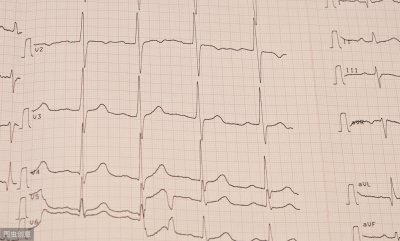

心律不齐 心律不齐是不是心脏病?有没有危险?医生说的明明白白 不少人在体检的时候,心电图上都会显示“心律不齐”的结果报告,这个结果让很多人感到恐慌,这个“心律不齐”...